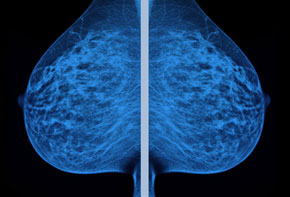

Ten years ago, DeLancey’s team began trying to figure out how to prevent some of these harms in the first place. Using state-of-the-art MRI techniques, the researchers identified one injury in particular that dramatically increases a woman’s odds of problems later on. At the base of the pelvis, there’s a small muscle called the levator ani that gets completely torn off the bone in about 15 percent of vaginal births. It takes training to detect the injury immediately after birth—few doctors know how to do so—and after six months or so, it becomes nearly impossible to spot. So the vast majority of women to whom this happens won’t know until years later, when they become incontinent or have a prolapse.

DeLancey and Dietz, working separately, found that certain women are much more likely than others to experience a levator ani tear. Pushing for two and a half hours or more is one risk factor, as are certain body types. Delivery with forceps is the biggest risk factor of all. DeLancey also co-authored a small 2015 study in which 29 percent of postpartum women at risk for levator ani tears were found to have fractures from childbirth.